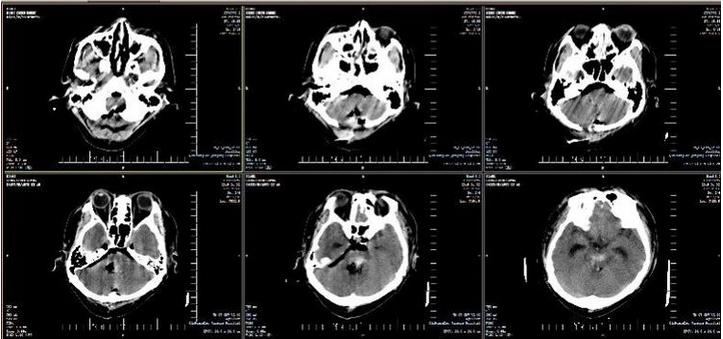

患者48岁,男性,突发昏迷,呼之不应,遂就诊于某医院,急诊头颅CT显示:脑干出血,不除外小脑、第四脑室内出血。入重症医学科治疗,给予降血压、止血、降颅压、营养脑细胞及维持电解质平衡等治疗,病情无好转,出现发热,给予气管插管接呼吸机辅助呼吸,病情危重,患者家属焦急万分,先后咨询多家医院,得到的答复全部都是“手术治疗没有任何意义”。后患者家属带头颅CT片来到秦皇岛军工医院咨询,神经外科主任进行紧急会诊。患者家属得知军工医院神经外科曾治愈多位脑干出血患者,听取医生的会诊意见后,积极要求在军工医院进行手术治疗。

2019年1月2日,军工医院副院长于笑鹏协调急诊科、重症医学科、神经外科、手术室麻醉科做好转接手术患者相关准备工作,紧急召集120急救人员与该医院沟通,将患者接到重症医学科进行术前准备。患者来院后复查头CT显示:脑干内血肿量较前明显增多,出现梗阻性脑积水征象。在院领导的关注下,神经外科医生团队经过两个多小时的精湛手术,患者生命体征平稳。复查头CT显示:脑干内血肿清除彻底,脑积水解除,转回军工医院重症医学科继续治疗。术后6小时,患者自主呼吸恢复,有吞咽动作,格拉斯评分由入院前3分转为5分,各种刺激检测均有反应。

术前ct片